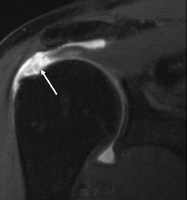

정상 어깨의 MRI 촬영 이미지(왼쪽)와 회전근개파열 어깨의 MRI 촬영 이미지(오른쪽)